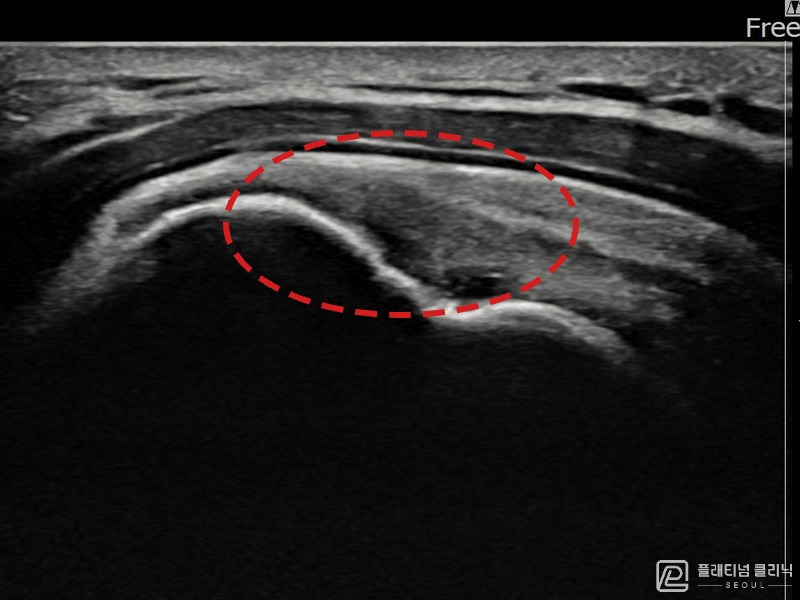

[촬영시기:22.10.06~22.11.14]

[어깨인대 축소봉합술] 좌측 어깨 극상근건 광범위 파열로 수개월간 일상생활이 어렵던 중 내원하셨습니다.